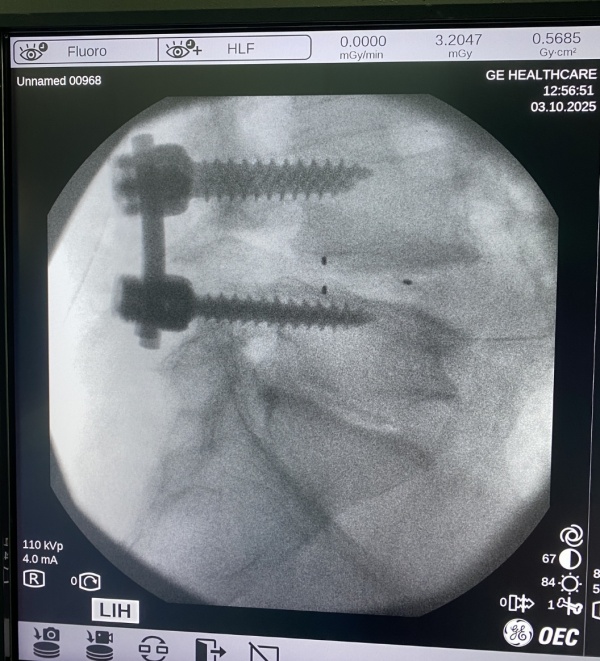

ESTENOSIS DE CANAL LUMBAR: para la resolución de este importante problema debemos liberar el canal lumbar, que se encuentra estrechado con compresión de las raíces nerviosas o la médula y en función del caso, realizar una ARTRODESIS VERTEBRAL (fijación de las vértebras para que no recidive la lesión). Este tipo de cirugía precisa ingreso de 4-5 días y la recuperación va desde 6 semanas a 3-4 meses por lo general.

Artrodesis lumbar